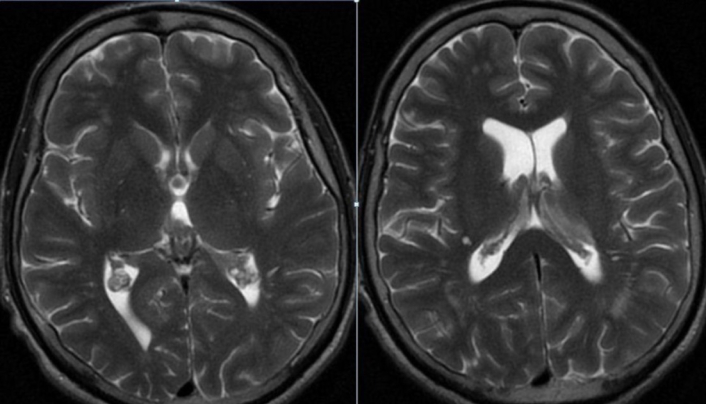

A 30-year-old male Lebanese patient was received at the emergency department initially manifesting mild headache and emesis over the weekend in the inaugural week of March 2023. Preliminary laboratory analyses yielded normative outcomes. A cranial computed tomography (CT) exhibited regular findings except for marginal engorgement of the choroid plexus within the lateral ventricles (Figure 1). Despite the absence of neurologic deficits, subsequent magnetic resonance imaging (MRI) disclosed a comparable indefinite irregularity of the choroid plexus (Figures 2 and 3). CSF examination demonstrated standard parameters for glucose, protein, white blood cells, and red blood cells. Additional inquiries, encompassing echocardiography and carotid imaging, yielded unremarkable results. The patient lacked notable medical history but exhibited elevated cholesterol levels and was on a regimen of aspirin 81 mg, clopidogrel 75 mg, and atorvastatin 40 mg. Following discharge with analgesic therapy, the family reported alleviation of the headache. However, a few days later, the patient revisited the emergency department with exacerbated cognitive impairment, confusion, and lethargy. A second urgent MRI unveiled heightened choroid plexus congestion and hypodense lesions in the pons (Figures 4 and 5). Lumbar puncture (LP) indicated elevated white blood cells, elevated glucose, and diminished protein levels, culminating in a vasculitis diagnosis. Steroid therapy, namely methylprednisolone 500 mg every 12 h, was initiated. Concomitantly, further deterioration of the neurological status of the patient ensued despite steroid therapy, leading to choroid plexus edema and hydrocephalus, necessitating ventriculoperitoneal shunt (VPS) placement. The patient’s condition deteriorated further, with a Glasgow Coma Scale score of 10, Karnofsky’s performance status at 10–20%, and Zubrod stage 4. An urgently conducted choroid plexus biopsy during the same procedure revealed evidence of diffuse large B-cell lymphoma (DLBCL). Postoperative complications in the intensive care unit necessitated a second VPS due to hydrocephalus and obstruction of the initial catheter by proliferating choroid plexus tissue (Figure 6). Despite diminished reflexes and increased oxygen requirements, the patient remained responsive to pain. DLBCL treatment involved intravenous methotrexate, intrathecal cytarabine, and rituximab, followed by 18 radiotherapy sessions. Post-chemotherapy, the patient exhibited confusion, short-term memory deficits, and orientation primarily toward immediate family members. However, a gradual improvement in neurological status was noted during the radiotherapy course. As of August 2023, the patient has completed the requisite radiotherapy sessions. During the last assessment in December 2024, the individual was conscious, cooperative, and oriented. Lingering minor lower limb weakness is progressively improving through physiotherapy. On the Karnofsky scale, the patient registers at 60%, corresponding to Zubrod stage 2.

Magnetic resonance imaging (MRI) of the head in axial view: T2-weighted sequence showing an increased isointense congestion of the choroid plexus: bilateral lateral ventricles